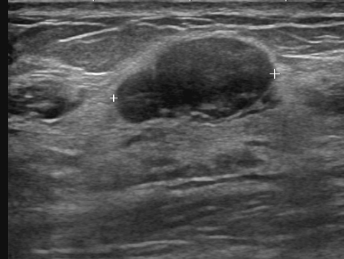

유방초음파는 초음파 검사 시 병원마다 약간의 차이가 있지만 기본 10만 원부터 시작하며 보험 미적용 대상입니다.

하지만 초음파 검사 비용에 건강보험을 적용할 시 약 4~8만 원 정도만 내면 됩니다.(60% 수준 감경) 정확한 금액은 의료기관별로 다릅니다.

검사할 때 건강보험 혜택이 적용되는 기준은 따로 있습니다. 우선 가장 보편적으로 사용하는 흑백 영상 초음파 장비는 건강보험이 적용됩니다. 단, 진단 결과에 따라서 양성이냐 악성이냐 여부에 따라 최종 결정됩니다.

1. 양성종양(섬유선종 등등), 비증식성 및 증식성 병변

3. 유방 영상진단 검사 시 미세석회화나 멍울 등 이상 소견이 있는 경우